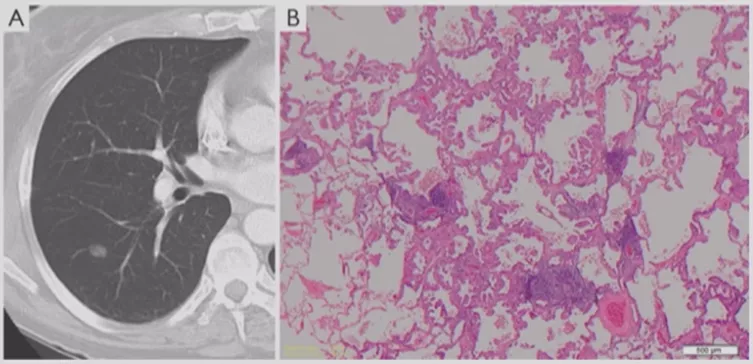

微浸润性腺癌(MIA)

进一步发展里面出现实性成分,或者结节的大小逐渐增大。微浸润性腺癌多位于肺外周,多为单发,一般<2cm,一般到了2cm就更严重了。最主要的是影像学多表现为边界清楚的部分实性结节,GGO比例>50%,实性成分多≤5mm。组织学上肿瘤细胞贴壁生长为主,多为非粘液型。此时要考虑微浸润的问题,这个时候手术效果还是非常好的。